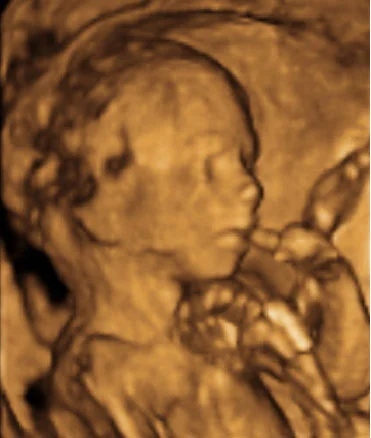

El feto mide unos 12 cm y pesa alrededor de 100 gramos. Sus rasgos faciales son más definidos, y comienza a formar expresiones faciales como fruncir el ceño. Los movimientos son más activos y coordinados. El sistema nervioso sigue desarrollándose y mejorando la conexión entre el cerebro y los músculos.

El feto mide aproximadamente 18 cm y pesa unos 350 gramos. Los movimientos del feto son más fuertes y frecuentes. El sistema nervioso sigue desarrollándose, y el feto ya puede experimentar el sentido del tacto. Las cejas y los párpados están completamente formados. El lanugo sigue cubriendo su cuerpo.

El feto mide alrededor de 19 cm y pesa unos 430 gramos. Sus labios y párpados están completamente desarrollados, y las uñas comienzan a crecer en los dedos de manos y pies. El cerebro continúa desarrollándose rápidamente. En esta etapa, el feto puede experimentar ciclos de sueño y vigilia, y sus movimientos siguen aumentando.